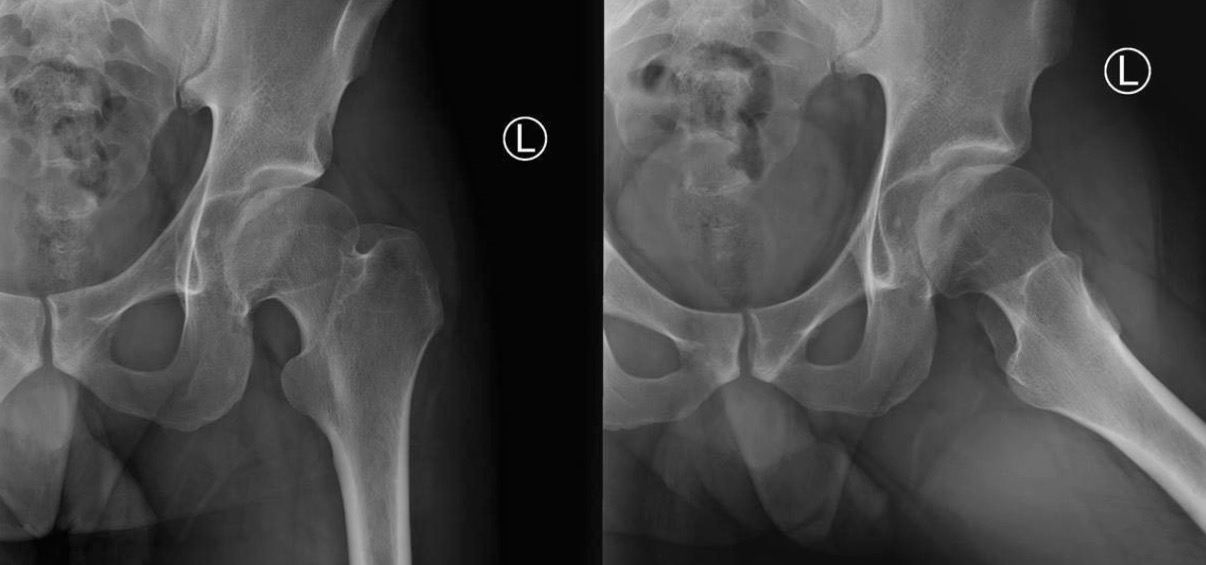

Диагностика дисплазии и импинжмента не такая сложная, на основании обычных стандартных исследовании. Прямой таз, прямой снимок каждого сустава и боковой, иногда требуется снимки в ротации: внутренняя и наружная, в аддукции и абдукции!

На представленном снимке (frog lateral) хорошо можно увидеть шейку и головку, но для данной патологии требуется false profile view! Для удобства приложил некоторые укладки: false profile и снимок с нормальными параметрами сустава (синими указаны центр край угол). Здесь имеется измененная и деформированная диспластическая форма головки, где огромный размер, выходя за пределы вертлужной впадины, создает иллюзию подвывиха. Очень узкая нагрузочная площадь и почти негативный (center-edge angle of Wiberg), потому что вертикаль (зеленая) от центра головки проходит с латеральной стороны. Контур передней стенки (синий) показывает что покрывает головку мало, а задняя стенка (красная) больших размеров доказывает что сустав развернут кпереди. Возможно за счет укладки, на рентгене слева шейка вроде короткая.

Для определения диагноза, кроме рентген снимков, необходим клинический осмотр. При таком суставе внутренняя ротация конечности увеличивается, а наружная ротация лимитирована. Чрезмерная флексия и ротация покажет симптомы повреждения лабрального хряща.

В данном случае имеется возможность сохранить сустав, рекомендуется остеотомия таза, которая увеличит нагружаемую поверхность и улучшит переднее покрытие. Тройная остеотомия имеет свои отрицательные стороны, например, из-за вовлечения задней колонны затягивается восстановление и бывают проблемы в акушерской практике. PAO (периацетабулярная остеотомия) таза позволяет исправить все деформации через один передний доступ.